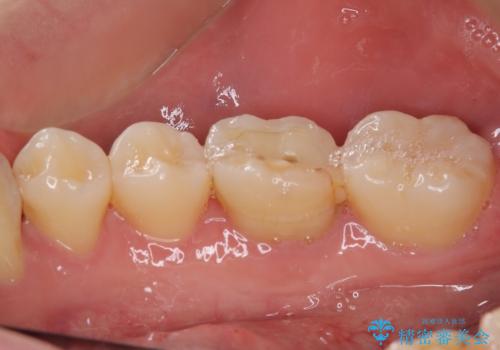

まずはしみる上顎の歯を仮歯に置き換え、その後下顎の根管治療を行った上で、異常が認められなければオールセラミッククラウンにて補綴治療を行うこととしました。

上顎は仮歯に置き換えた後に、それまでの痛みは一切感じなくなり、下顎も一度目の根管治療で痛みを感じることはなくなりました。